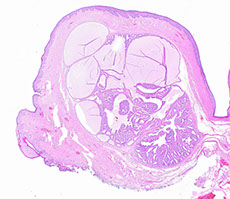

Appendix histology

This wormlike (vermiform), 7-10 cm long structure usually comes about 1-3 cm before ileocecal junction at junction of 3 cecal/ ascending colon teniae.

Histo similar to that of large bowel.

From lumen out: Mucosa, Submucosa, Muscularis externa, Serosa

Mucosa

Surface epithelium

- Columnar cells: eosinophilic cytoplasm and basally located nucleus. Includes absorptive cells and M cells

- Goblet cells: mucin droplet stains with PAS and Alcian blue. Seen more often in the crypts than in suface epithelium.

- M (Membranous) cells: Columnar, brush border, surround lymph aggregates to help bring in antigens. Can usually find lymphos between them.

--Usually fewer crypts between these M cells and lymph aggregates than in other parts of the appendix

-Crypts spread more unevenly than in colon. Work in cell renewal.

-- Endocrine cells: Flasked-  to spindle-shaped. May/not have luminal connection, respectively. (+) chromogranin stain. Found isolated/clustered throughout crypts

-- Paneth cells: abundant eosinophilic supranuclear granules. Found in crypt bases. Function unknown.

- Collagenous subepithelial BM. (+) PAS

-Lamina propria: made of collagen, fibroblasts, VANs, numerous lympho cells. Found in center of mucosa, though can be distorted by lymph aggregates.

-Lymph aggegates: absent at birth, peak in 1st decade then diminish. Similar to Peyer's patches in structure/function. though more cells in appendix have IgG than in colon.

-Mucosal neuroendocrine complex: polygonal cells w/ pale granular cytoplasm beneath crypts. Have neurosecretory cells, neurons, and Schwann cells (thus (+) S-100).

-Muscularis mucosae: continuum from colon, though weaker in appendix, to separate mucosa/submucosa.

Submucosa

Collagenous/ elastic fibers w/ fibroblasts between mucosa and muscularis externa. Also see migratory cells, VANs, Meissner's plexus (ganglion cells, Schwann cells, neurons).

Muscularis externa

Thick double sm. muscle (inner circular, AUERBACH, outer longitudinal) that separates submucosa / serosa. Auerbach's plexus found between 2 sm. musc layers.

Serosa

Nonstratified cuboidal mesothelial cells on top of loose CT of subserosa.

- Attachment of fibrofatty mesoappendix lacks a serosa